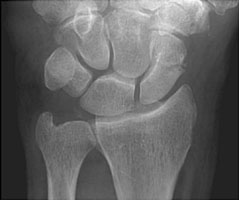

Scaphoid fractures are the most common carpal fractures, resulting from a fall on an outstretched hand. 70 % of these occur at the waist, 20 % at the proximal pole, and 10 % at the distal pole. Blood supply for the proximal pole enters at the waist. If this blood supply is interrupted due to fracture, the proximal pole is at risk for avascular necrosis. Special scaphoid views with the hand in ulnar deviation may be needed to detect these fractures.

- Click on the image for a larger versionCPA radiograph of the wrist. Another patient shows the proximal pole to be dense and has undergone avascular necrosis. This is a known complication of waist fractures.